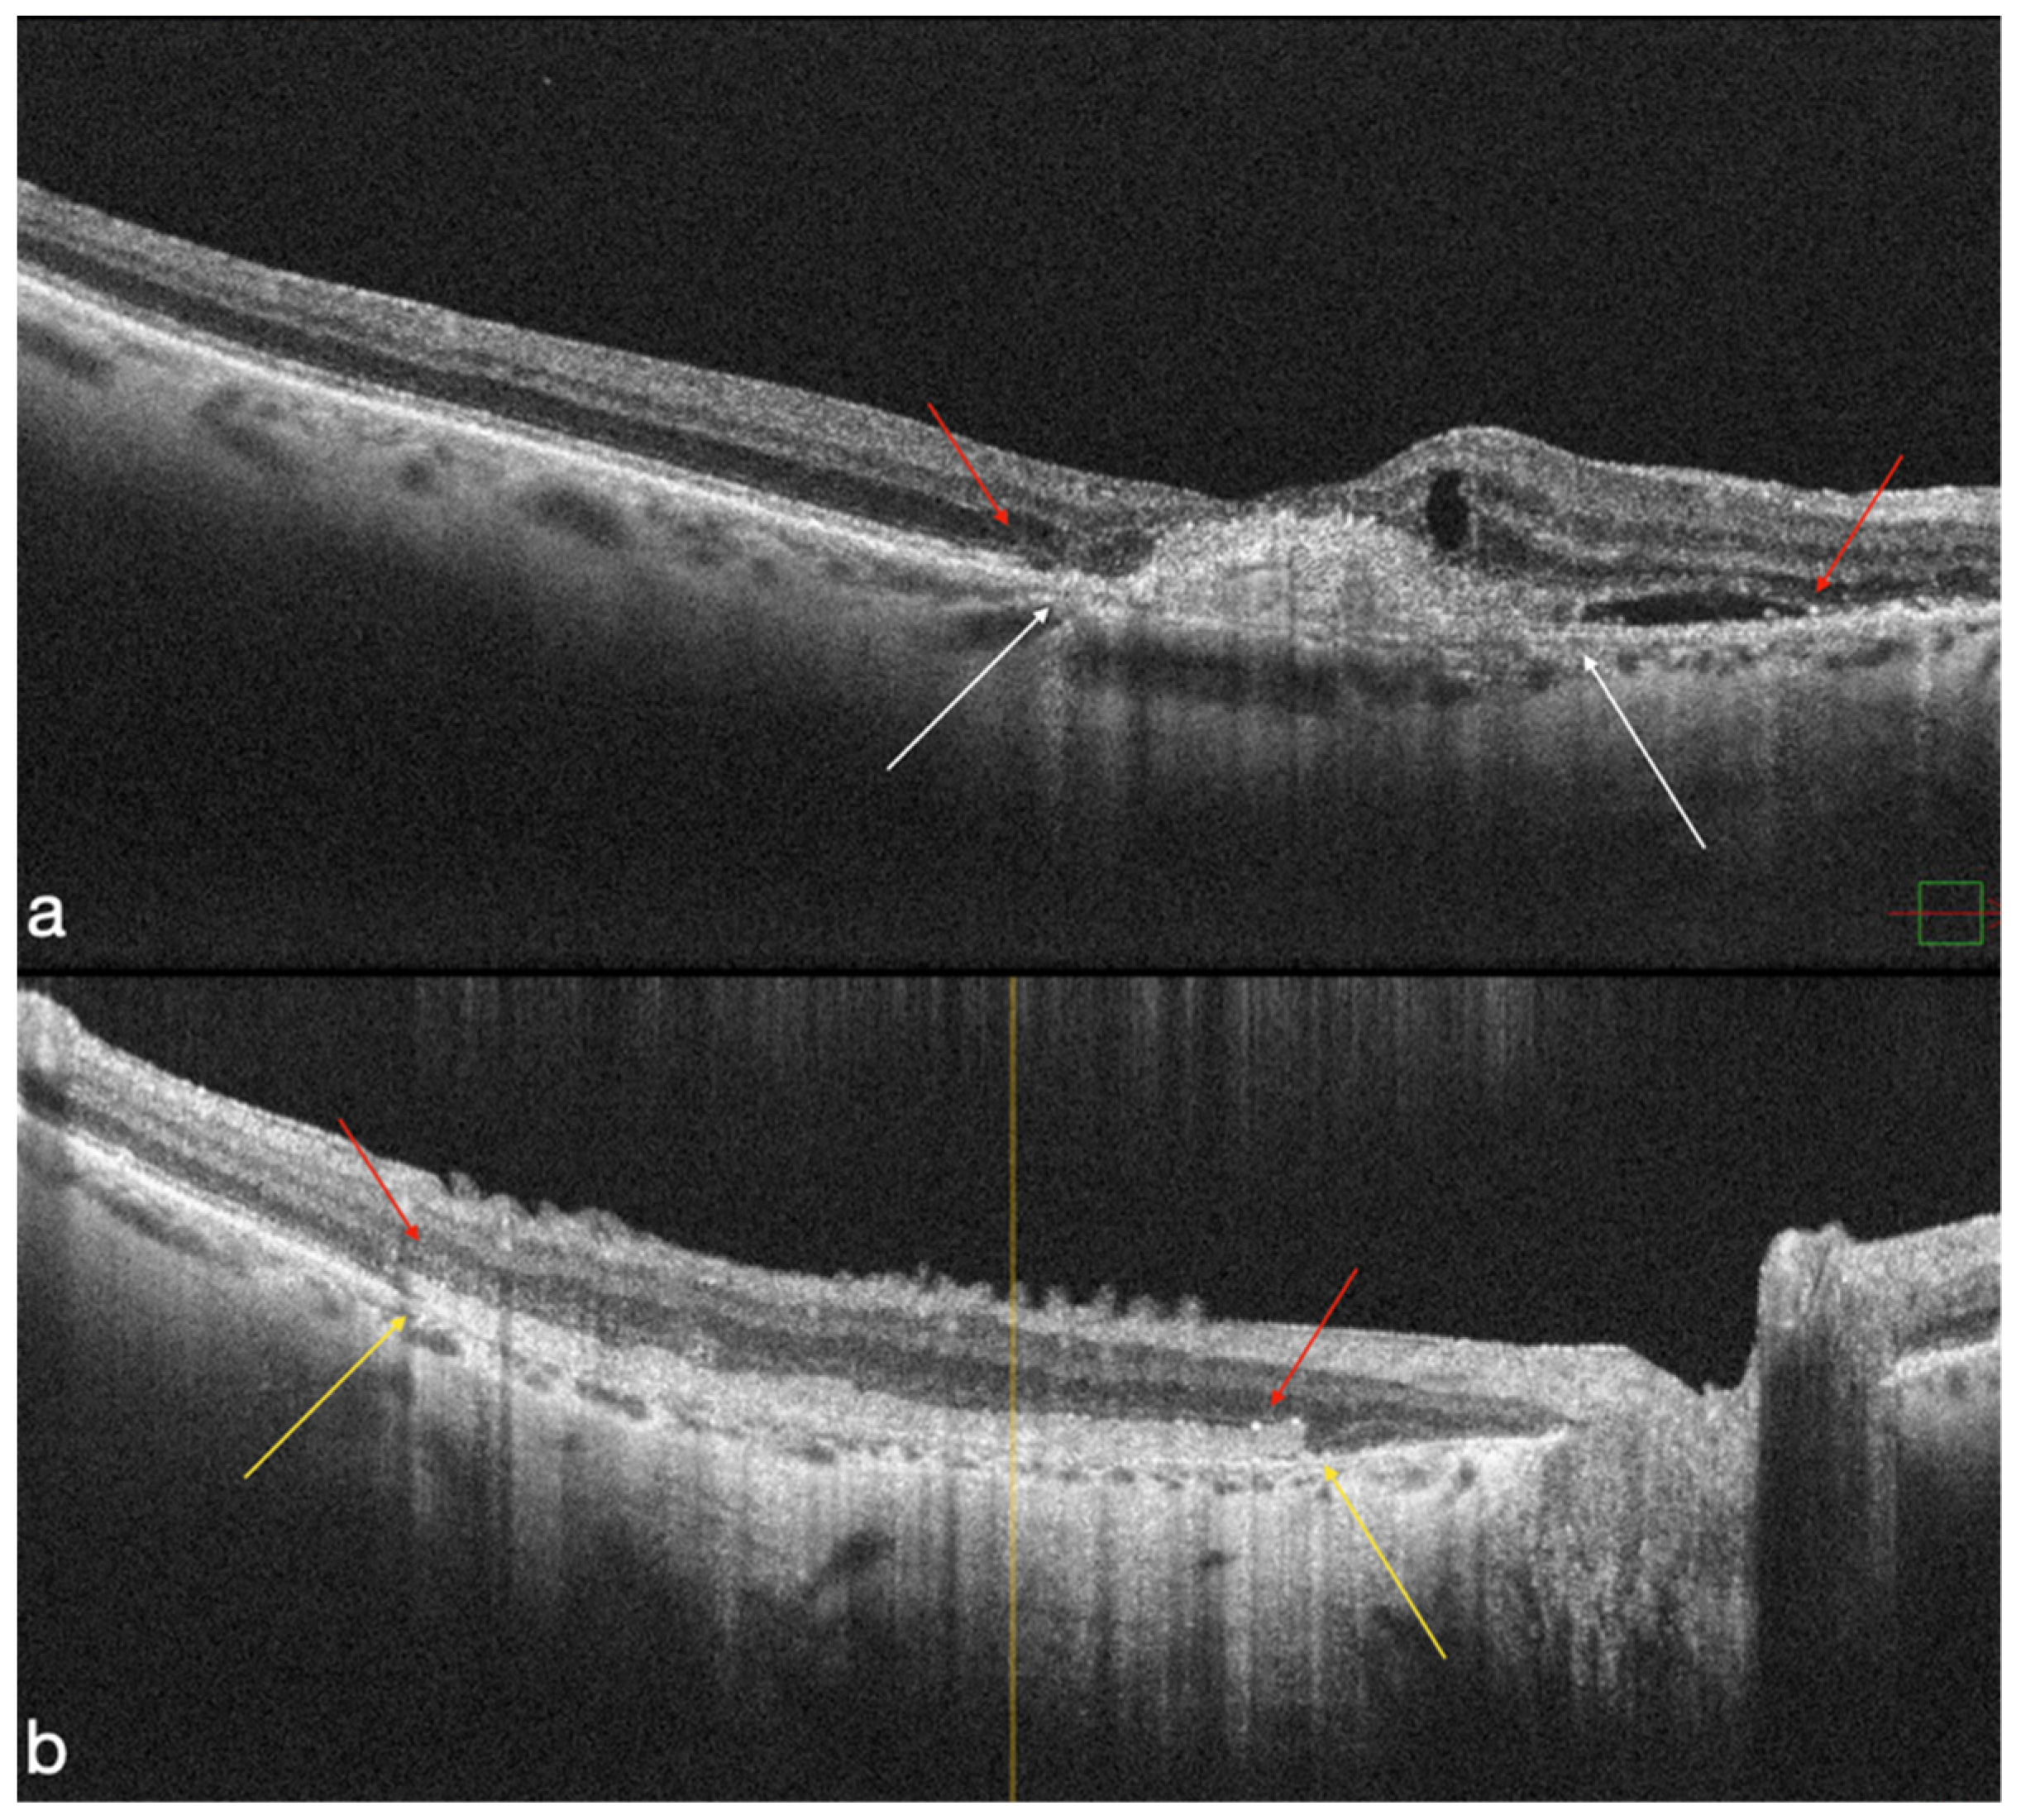

4.1. MNV-Group

4.2. Atrophic Group

4.3. OCT-A Results